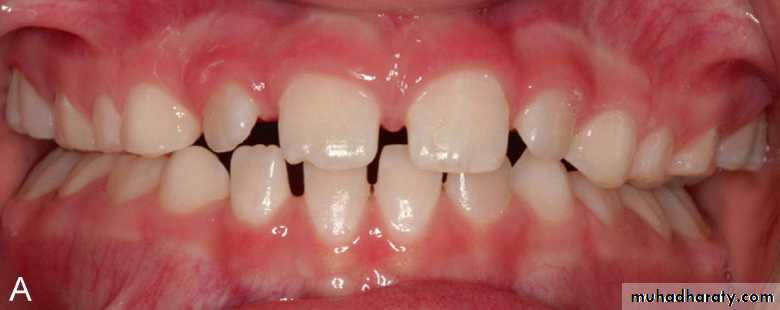

Posterior crossbite should be treated as early as possible even in the primary dentition.Early correction will eliminate mandibular shift on closure and reduce the possibility of mandibular skeletal asymmetry.

Correcting posterior crossbite in the mixed dentition increases arch circumference and provides more room for the permanent teeth to erup.

Reduces dental arch distortion.